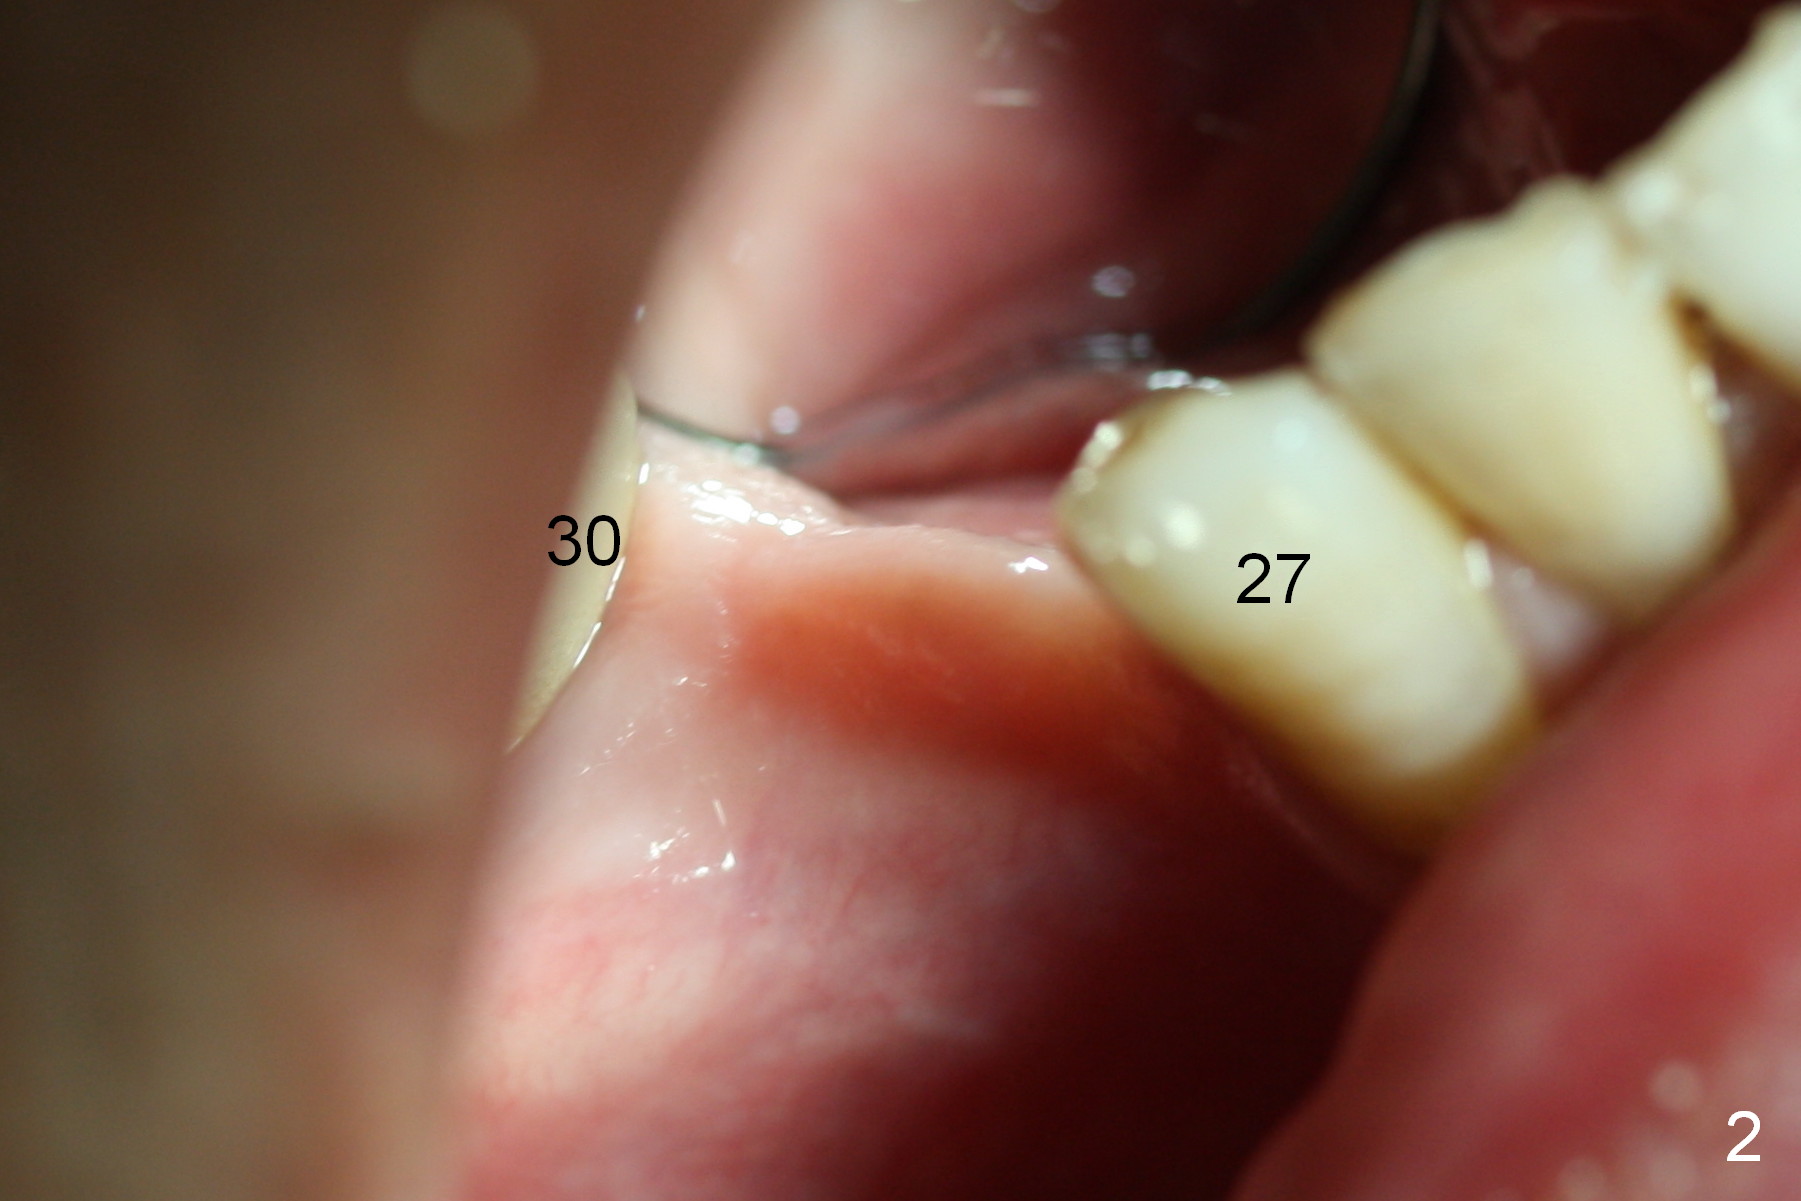

The patient has lost several teeth, which are replaced by removable partial dentures. He wants to have implants in the lower right first because of loss of a buccal clasp over the tooth #30 (Fig.1). When the lower partial is removed, a narrow soft tissue band is visible in the edentulous area. The hard tissue ridge is approximately 3 and 5 mm buccolingually at the sites of #28 and 29, respectively (Fig.3 after initial osteotomy). To place 2 adjoining implants at the same level, the treatment plan is modified: a 3 mm 1-piece implant will be placed at #28, while the plan at #29 remains the same: a 4.5 mm 2-piece implant.